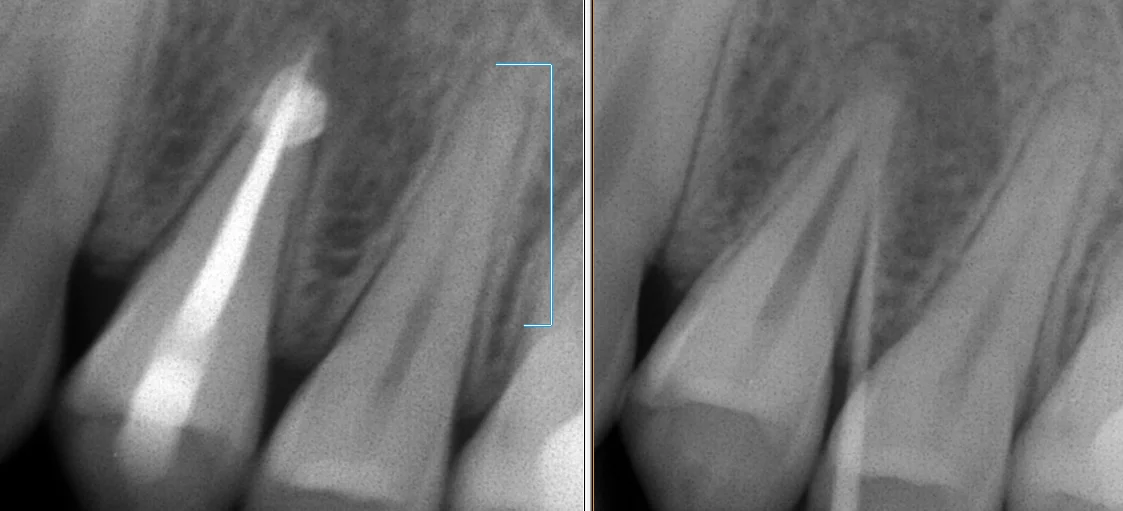

今回は神経の治療が終わった時のレントゲンからです。

右が術前に膿の袋にレントゲンに写る柔らかい棒状のものを刺してレントゲンを撮ったもの。

左が最終的なお薬を詰め終わったところです。

口の中にある、ニキビのようなところにこういう材料を入れて撮影することで、その膿がどの歯・どの根から出てるのかを判断できるので、非常に便利です。

デメリットは変なところに刺さると痛いことですね・・・(;'∀')

今回の場合だと、根っこが2本ありますが、そのうちの1つの方がニキビの原因になっている状態でしたね。

そして、お薬を詰め終わった写真がこちらです。